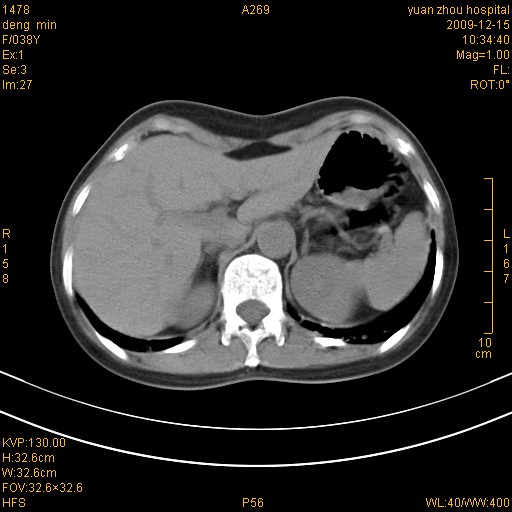

标题: CT23919:F38Y 咳嗽月余 [打印本页]

标题: CT23919:F38Y 咳嗽月余

右肺中下叶、左肺上叶舌段及左肺下叶支气管扩张合并感染。